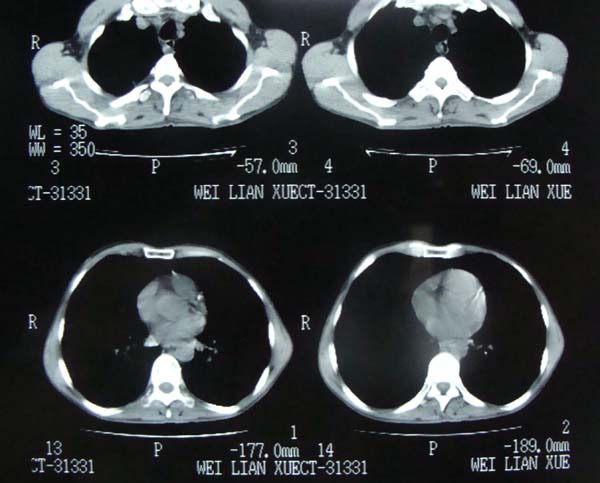

以下是引用pujunzhi在2009-6-21 21:48:00的发言:[br]右肺上叶后段见一空洞性病灶,灶周有渗出即晕征,右肺门肿大---可考虑感染性空洞和癌性空洞,先抗炎抗痨后复查并完善相关检查。有癌性空洞伴肺门淋巴结转移的可能。

以下是引用宝天曼在2009-6-21 22:48:00的发言:[br]首先考虑肺tb

以下是引用泪洒红尘在2009-6-21 21:55:00的发言:[br]考虑结核合并感染。